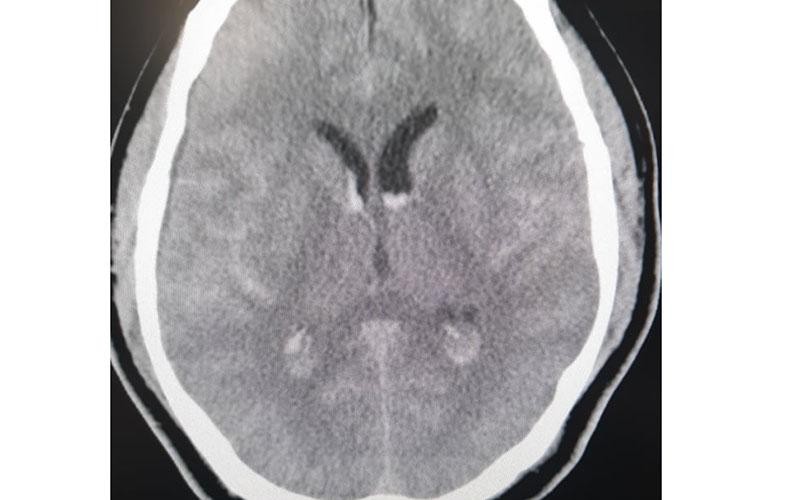

Hình ảnh phim chụp xuất huyết dưới nhện lan tỏa - tụ máu não thất. (Ảnh: Nhân Dân)

Ngày 9-12-2020, khi đang cùng nhóm đối tác đang chơi gôn ở Hòa Bình, đột ngột bệnh nhân cảm thấy đau đầu dữ dội, buồn nôn và nôn nhiều. Sau khi được đưa vào cấp cứu tại Bệnh viện đa khoa tỉnh Hòa Bình, bệnh nhân được chẩn đoán chảy máu dưới nhện thể nặng.

Theo các bác sĩ bệnh viện Bạch Mai đây là một ca đột quỵ nặng, bệnh nhân sẽ tử vong nếu không được can thiệp cấp cứu. Tổn thương của bệnh nhân nằm ở vị trí khó, phức tạp và nguy hiểm, thường cần một bác sĩ chẩn đoán hình ảnh chuyên sâu và nhiều kinh nghiệm mới chẩn đoán được.